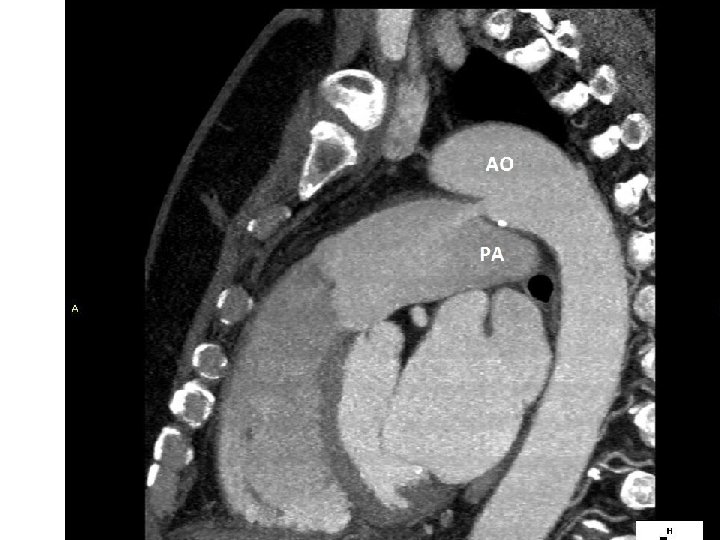

Transpozice velkých cév – Jatene operace